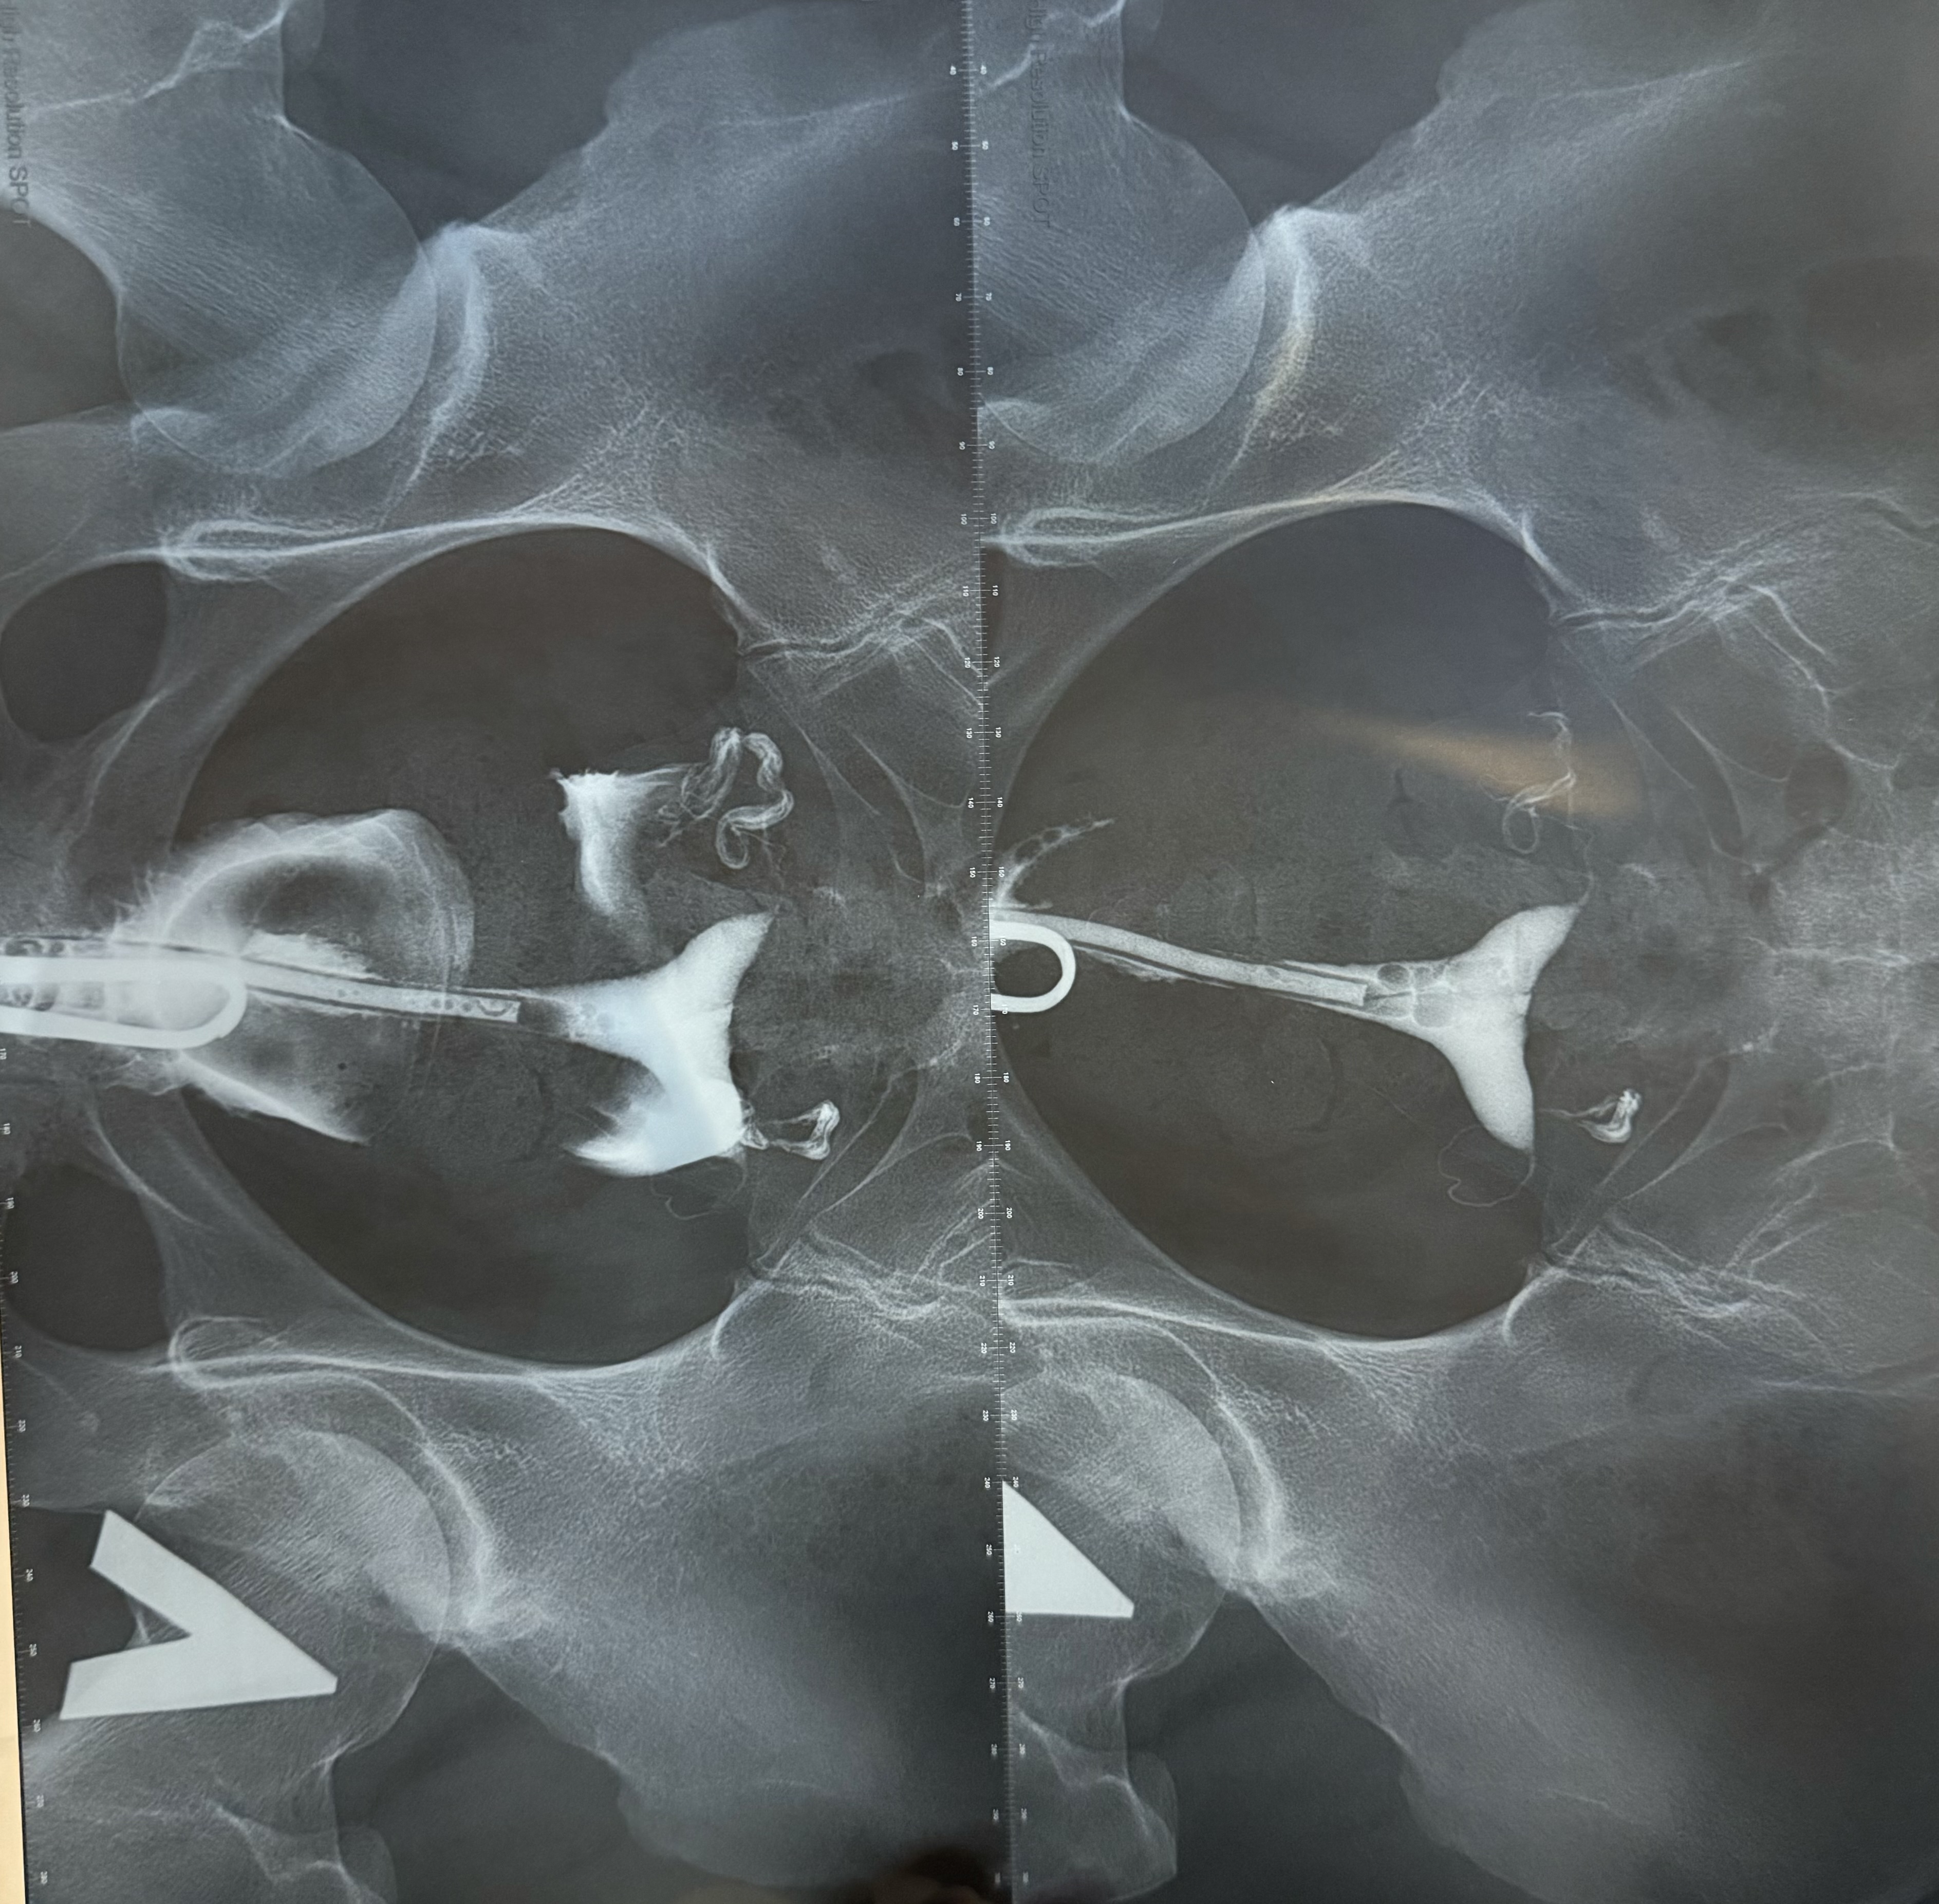

Я это сделала) ГСГ

Сегодня сделала ГСГ под седацией

врач сказала, что вроде трубы проходимы, но что-то в заключении рентгенолога немного другое

прикладываю заключение, может кто посмотрит, скажет, что это все значит

Трубы проходимы, но контраст когда выходит в брюшную полость не свободно по ней расходится, это признак спаечного процесса в малом тазу. У меня было так же, позже на ларароскопии подтвердилось.